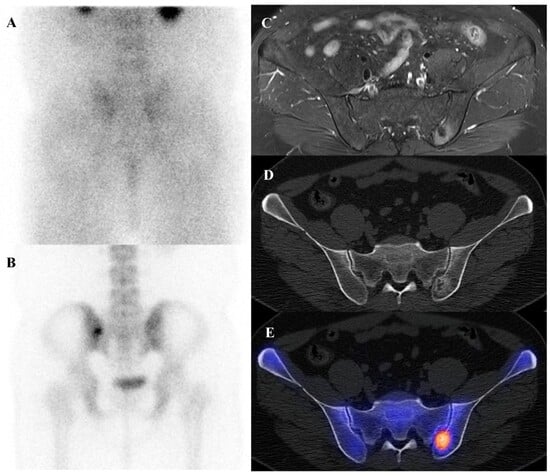

Patients with Ewing sarcoma are at high risk for disease recurrence, which most often occurs in the lungs or bone and carries a poor prognosis [45,46]. [18F]FDG PET/CT is an extremely valuable tool for post-treatment surveillance and for the early detection of recurrent disease [18,25]. The appearance of new, focal [18F]FDG-avid lesions on follow-up scans is highly suspicious for recurrence and prompts further investigation and salvage therapy. Whole-body nature of [18F]FDG PET/CT is ideal for detecting recurrence at any potential site. Figure 2 demonstrates a representative case in which bone scintigraphy failed to reveal recurrent disease, whereas [18F]FDG PET/CT clearly identified the metabolically active presacral mass, subsequently confirmed as recurrent Ewing sarcoma after surgical excision.

Figure 2.

A 19-year-old female with recurrent Ewing’s sarcoma. (A,B) Bone scintigraphy shows no abnormal uptake on both anterior and posterior view. (C) T1 fat-suppressed magnetic resonance imaging demonstrates a lobulated, enhancing presacral mass with invasion of the sacrum. (D–F) [18F]FDG positron emission tomography/computed tomography reveals intense uptake of the mass (SUVmax 9.0). Surgical excision confirmed recurrence of Ewing’s sarcoma.